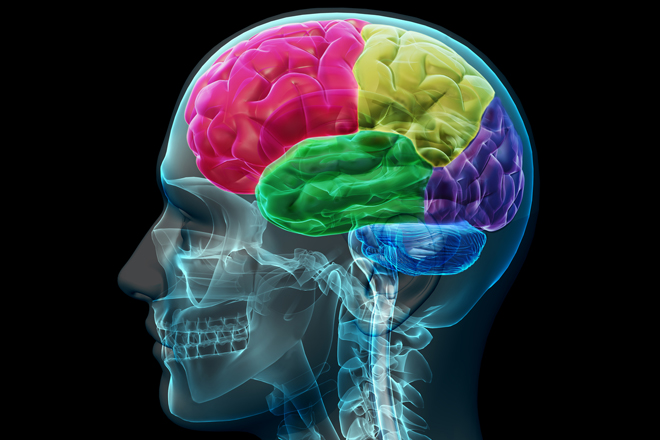

El cerebro humano es la estructura biológica más compleja en la Tierra. Tiene cerca de 100 mil millones de neuronas, cada una de las cuales tiene miles de conexiones con otras neuronas.

Por otra parte, los cerebros cambian con el tiempo por una variedad de razones. Por ejemplo, a medida que envejecemos, nuestro cerebro pierde células nerviosas (neuronas). Además, el cableado de nuestro cerebro se altera continuamente a medida que aprendemos, socializamos, experimentamos estrés y encontramos diversas condiciones ambientales. Así es: Nuestros cerebros están anatómicamente y fisiológicamente cambiados por experiencias intelectuales y físicas normales.

Así que cada uno de nosotros tiene un único cerebro. De hecho, incluso los cerebros de los gemelos idénticos difieren el uno del otro. Lo que es más, las lesiones cerebrales pueden provocar diversos tipos de cambios en la anatomía y la fisiología del cerebro para compensar la función perdida y/o maximizar las funciones restantes. En efecto, nuestra comprensión del cerebro sigue siendo francamente rudimentario en comparación con el conocimiento de otros órganos.

A pesar de los grandes avances tecnológicos en la investigación del cerebro durante las últimas décadas, los científicos todavía tienen que describir todos los diversos tipos de células que componen el cerebro y determinar sus funciones. Para complicar más las cosas, el cerebro es más que la suma de sus partes. Es decir, los diversos componentes del cerebro no funcionan de manera aislada unos de otros, sino que deben comunicarse entre sí y trabajar juntos para procesar la información y producir memorias, pensamientos y comportamientos.